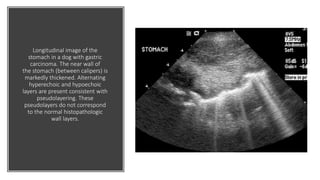

Longitudinal image of the

stomach in a dog with gastric

carcinoma. The near wall of

the stomach (between calipers) is

markedly thickened. Alternating

hyperechoic and hypoechoic

layers are present consistent with

pseudolayering. These

pseudolayers do not correspond

to the normal histopathologic

wall layers.

Longitudinal image ofthe stomach in a dog with gastric carcinoma. The near wall of the stomach (between calipers) is markedly thickened. Alternating hyperechoic and hypoechoic layers are present consistent with pseudolayering. These pseudolayers do not correspond to the normal histopathologic wall layers.